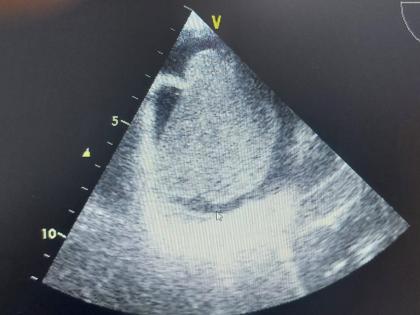

रूग्णालयातील कार्डिओव्हस्कुलर आणि थोरँसिस सर्जन डॉ. उमेंद्र भालेराव म्हणाले की, “ज्या वेळी या महिलेला रूग्णालयात आणण्यात आले होते तेव्हा या महिलेला श्वास घेताना त्रास जाणवत होता आणि पायाला सूज होती. त्यांना ऑक्सिजनवर ठेवण्यात आले होते. अशा स्थितीत डॉ. अनुप टकसांडे यांनी या महिलेची इकोकार्डिओग्राफी तपासणी केली. या चाचणीत महिलेच्या हृदयाच्या उजव्या वरच्या भागात ७ सेंटिमीटर इतक्या मोठ्या आकाराची गाठ असल्याचे निष्पन्न झाले. यामुळे हृदयाव्दारे शरीरातील अन्य अवयवांना होणाऱ्या रक्तप्रवाहात अडचणी येत होत्या. फुफ्फुसाला योग्यपद्धतीने रक्तपुरवठा होत नव्हता. मायक्सोमा नावाचा हा हृदयाचा ट्यूमर होता. या आजारावर वेळीच उपचार न झाल्यास रूग्ण दगावू शकतो.”